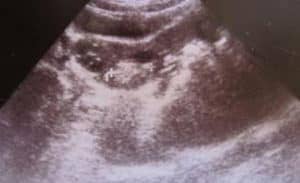

Quiste hemorrágico

Tal neoplasia del apéndice se forma después de una hemorragia en el cuerpo lúteo o en el quiste folicular. En este caso, se produce un síndrome de dolor agudo en la parte inferior del abdomen, pero a veces se observa un curso asintomático de la patología. Cuando la cavidad se rompe, la sangre se acumula en el área del órgano genital y los apéndices.

En la ecografía, un quiste hemorrágico aparece como una formación de una sola cámara con una suspensión hiperecogénica. Los hilos de fibrina se transforman en una malla calada. A veces, una inclusión tan extraña parece densa. No hay flujo de sangre en su interior, pero a lo largo de la periferia se puede rastrear.